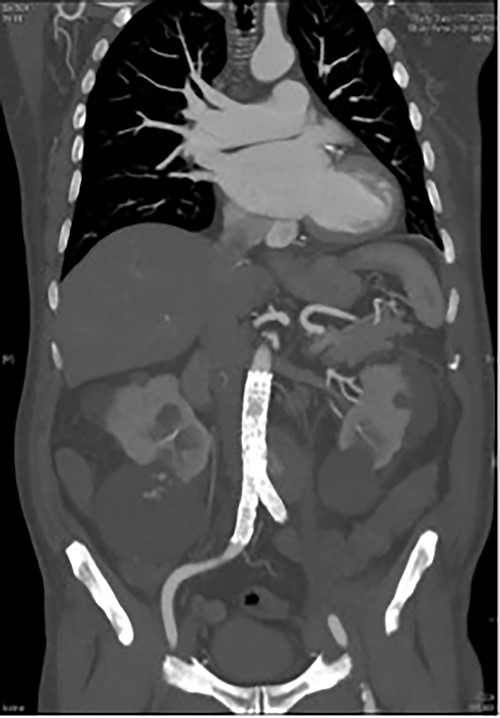

A 73-year-old male presented with a 1-week history of back pain on a background of hypertension, atrial fibrillation and bladder cancer. Computed tomography (CT) angiography demonstrated a 47 × 46 × 47 mm saccular aortic pseudoaneurysm of the infrarenal aorta with a contained rupture (Fig. 1). The patient remained hemodynamically stable with mildly elevated inflammatory markers (C-Reactive Protein (CRP), 85 mg/l, white cell count (WCC) 6.5 × 109/l). The abdominal aorta 5 months previously was normal on CT when a course of intra-vesical BCG for transitional cell carcinoma of the bladder had been ceased due to the development of fevers and syncope. Thus, Mycobacterium bovis involvement of the false aneurysm was suspected. Emergent endovascular repair was performed with a covered stent graft system successfully excluding the ruptured aneurysm sac on post-operative CT angiogram. A CT-guided fine needle aspirate of the aneurysmal sac was later conducted (Fig. 2). PCR of the aspirate returned a low-positive result confirming the diagnosis with M. bovis subsequently isolated on culture. Empirical antibiotics were ceased and he was commenced on a planned 18-month antituberculosis regimen of ethambutol, isoniazid and rifampicin guided by gene deletion analysis (GeneXpert MTB/RIF Ultra assay). Fluorodeoxyglucose-positron emission tomography (FDG-PET) scan was used to monitor the level of activity of the infection (Fig. 3). The patient was discharged home on Day 10 of admission. Aneurysm sac size was decreased at 3 and 6 months on CT angiogram and FDG-PET but there was ongoing FDG avidity around the aneurysm sac; there were no other sites of involvement. The patient remains otherwise well and has returned to his premorbid activities.

CT aortic angiography demonstrating a 47 × 46 × 47 mm infrarenal aortic pseudoaneurysm with an area of contrast filling and associated mass displacement of the aorta and inferior vena cava. (A) Coronal and (B) sagittal.